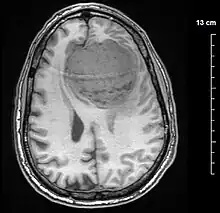

| A contrast-enhanced CT scan of the brain, demonstrating the appearance of a meningioma | |

Meningiomas are visualized readily with contrast CT, MRI with gadolinium,[22] and arteriography, all attributed to the fact that meningiomas are extra-axial and vascularized. CSF protein levels are usually found to be elevated when lumbar puncture is used to obtain spinal fluid. On T1-weighted contrast-enhanced MRI, they may show a typical dural tail sign absent in some rare forms of meningiomas.[17]